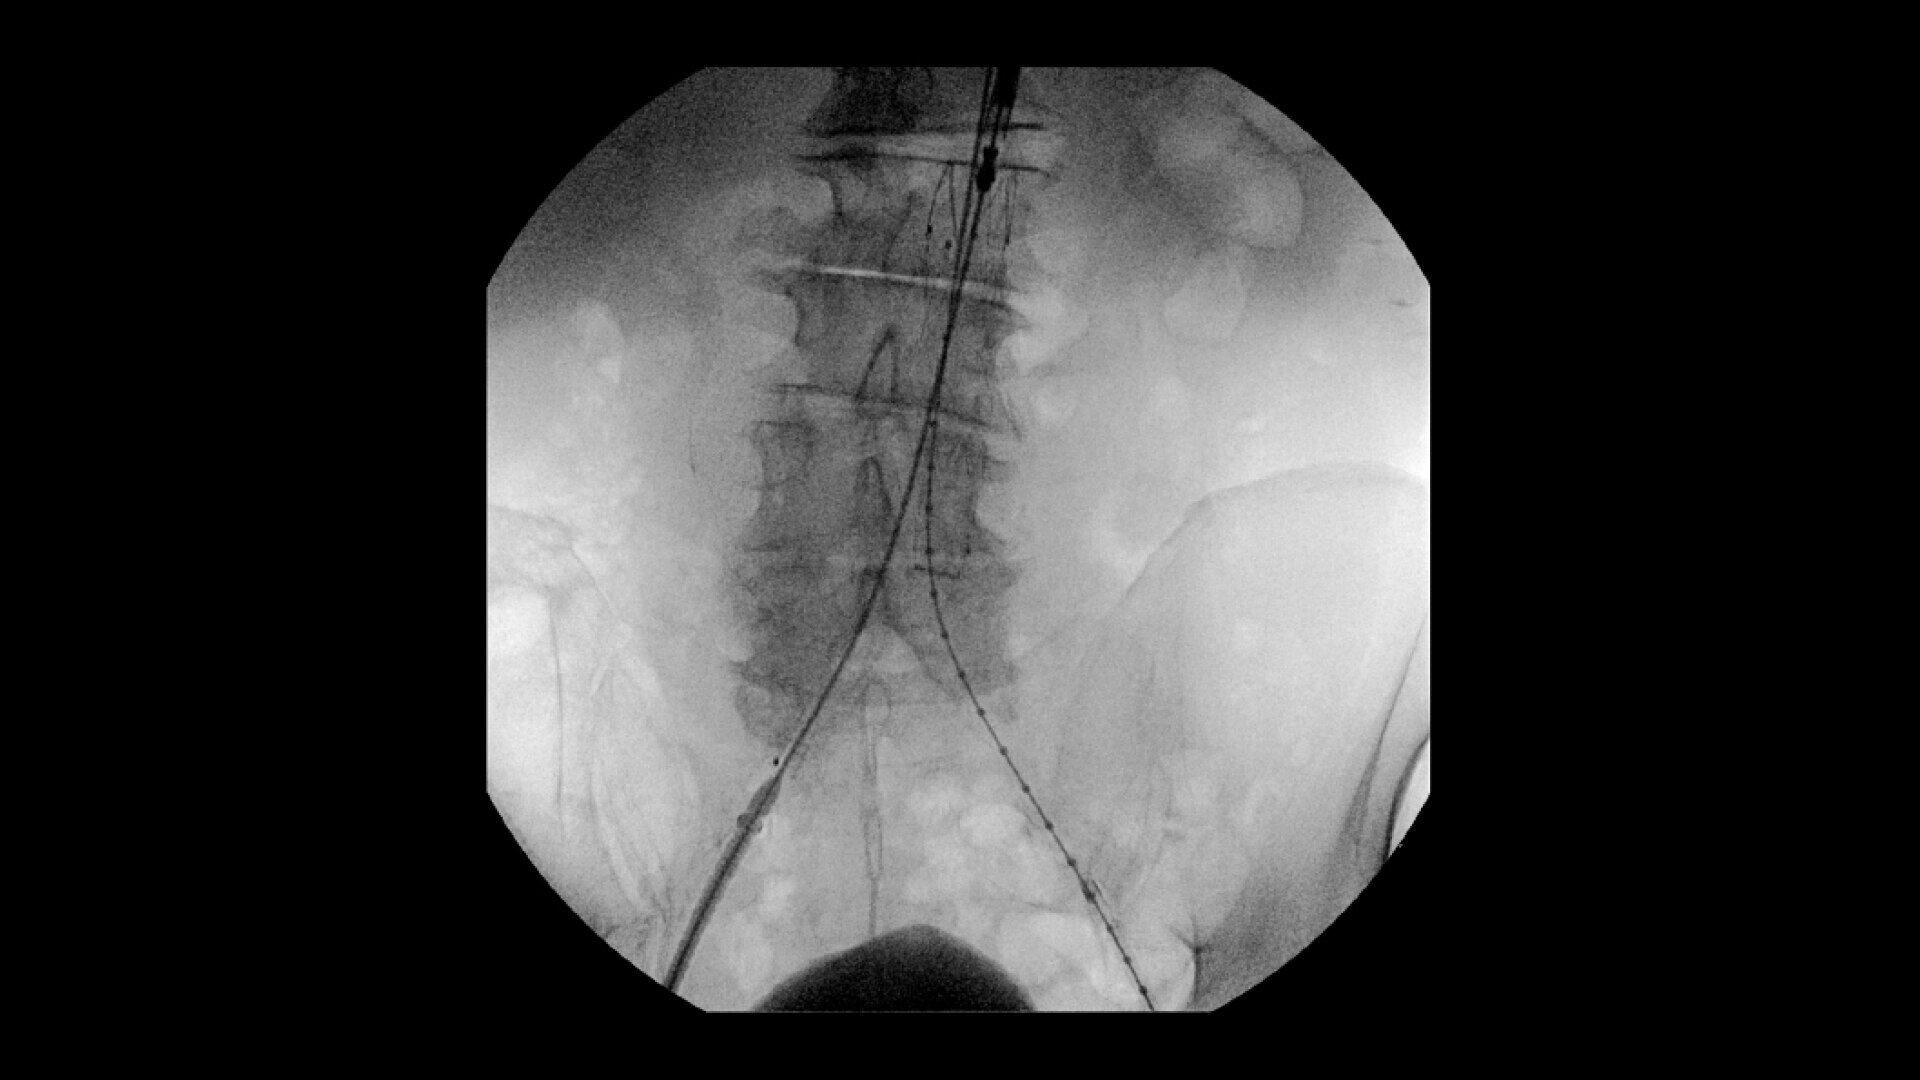

Perform a full leg Bolus Chase in one contrast run with a Preset Profile that includes Motion Tolerant Subtraction, that dynamically adjusts image quality based on presence of motion.

During contrast run-off procedures, easily select contrast type with positive (e.g. Iodine) or negative (e.g. Carbon Dioxide) during subtraction. The OEC Elite CFD cardiovascular package also includes Roadmapping.

To see vessel stenosis or tips of guidewires, Live Zoom up to 4X during a fluoro or Cine without the additional dose of Mag modes or resulting X-ray tube heat buildup.

Conveniently plan procedures with comprehensive imaging tools to measure percent stenosis, distance, or angles, annotate and draw on images.

•Abdominal aortic aneurysm (AAA) stent and balloon deployment

• Infrarenal aortic aneurysm repair

• Recanalization and stent placement in iliac arteries